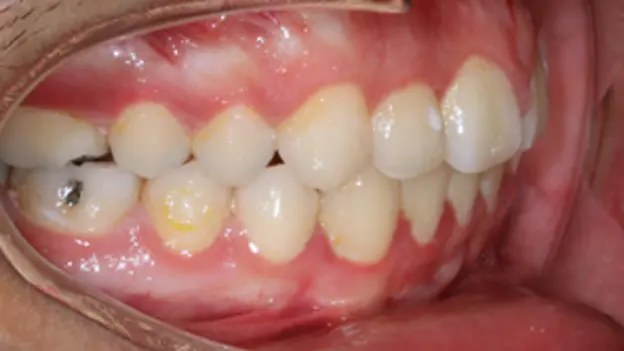

Before

After